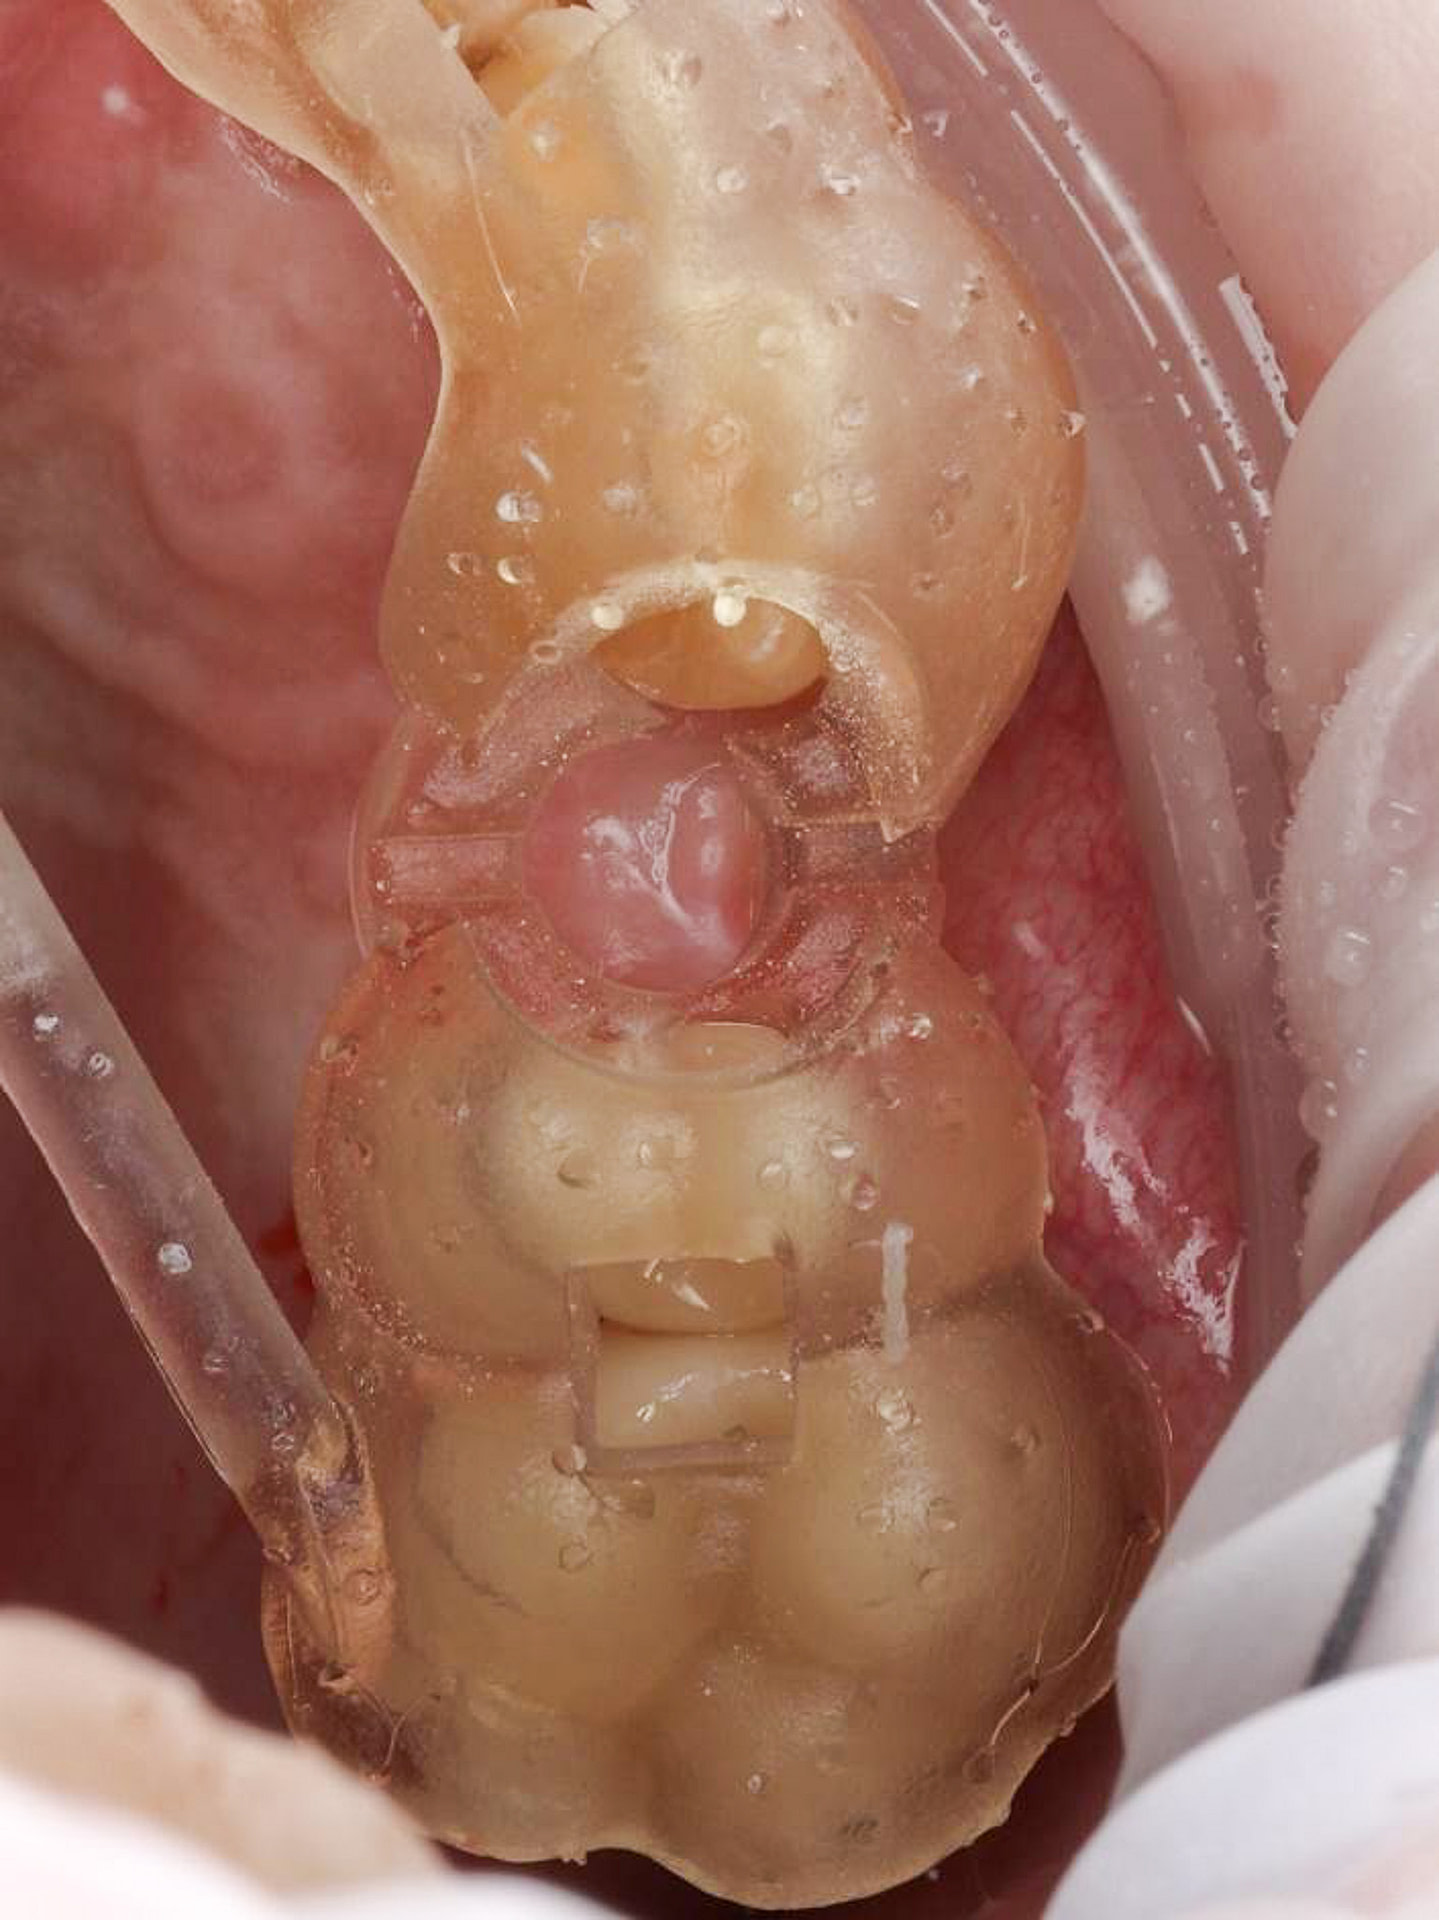

Upon examination by his previous dentist, a vertical root fracture was diagnosed, necessitating a surgical extraction. The procedure, which involved removing the buccal cortical bone, left the patient with a bony defect in the area of the extracted tooth.

His previous dentist retired, and the patient visited me for the first time as an emergency visit due to symptomatic irreversible pulpitis from a cracked tooth (46). Root canal treatment on tooth 46 was completed, and a crown placed.

Upon completing a comprehensive examination, it was revealed that teeth 25 and 26 were also cracked, and the patient expressed interest in replacing the missing tooth 24.